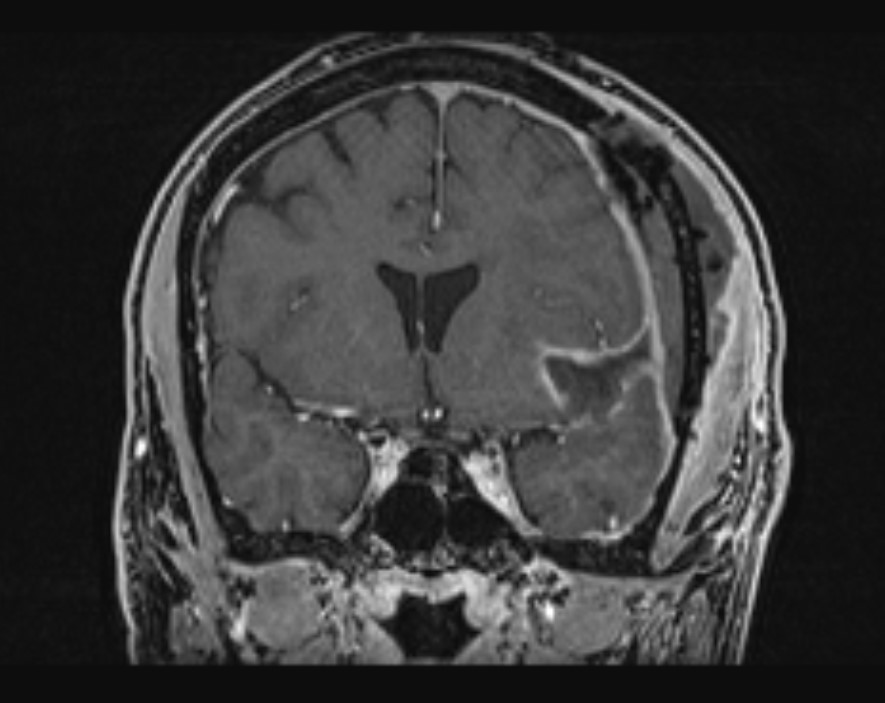

Το δόγμα της σύγχρονης χειρουργικής όγκων απεικονίζεται στις μαγνητικές αυτές. Στόχος μας είναι η μέγιστη δυνατή ασφαλής αφαίρεση του όγκου. Δεν πρέπει να στοχεύουμε στην εξαίρεση όχι μόνο του όγκου, όπως φαίνεται στην μαγνητική αλλά και στην αφαίρεση και της διηθητικής ζώνης και της υγιούς περιβάλλουσας περιοχής αν αυτή δεν έχει λειτουργίες. Η εικόνα 1α είναι προεγχειρητική, εδώ έχει σχεδιασθεί το εύρος της στοχευμένης εξαίρεσης. Η εικόνα 1β δείχνει το μετεγχειρητικό αποτέλεσμα μιας υπερολικής εξαίρεσης. Πρόκειται για την πρώτη ασθενή που χειρουργήθηκε στην Ελλάδα από τον Καθ. Γούσια τον Οκτώβριο του 2023, η οποία διαγνώσθηκε με την πιο επιθετική μορφή του γλοιοβλαστώματος, το λεγόμενο γλοιοσάρκωμα, η οποία 20 μήνες μετά την χειρουργική επέμβαση παραμένει χωρίς ένδειξη όγκου στην μαγνητική και το πιο σημαντικό χωρίς νευρολογικά ελλείμματα.